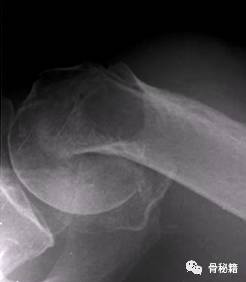

病例1

4部分骨折

解剖钢板与提拉螺钉的复位

需要注意 不要应用过度提拉 使得内侧肱骨距过复位

注意完成内侧支撑和内外翻的复位